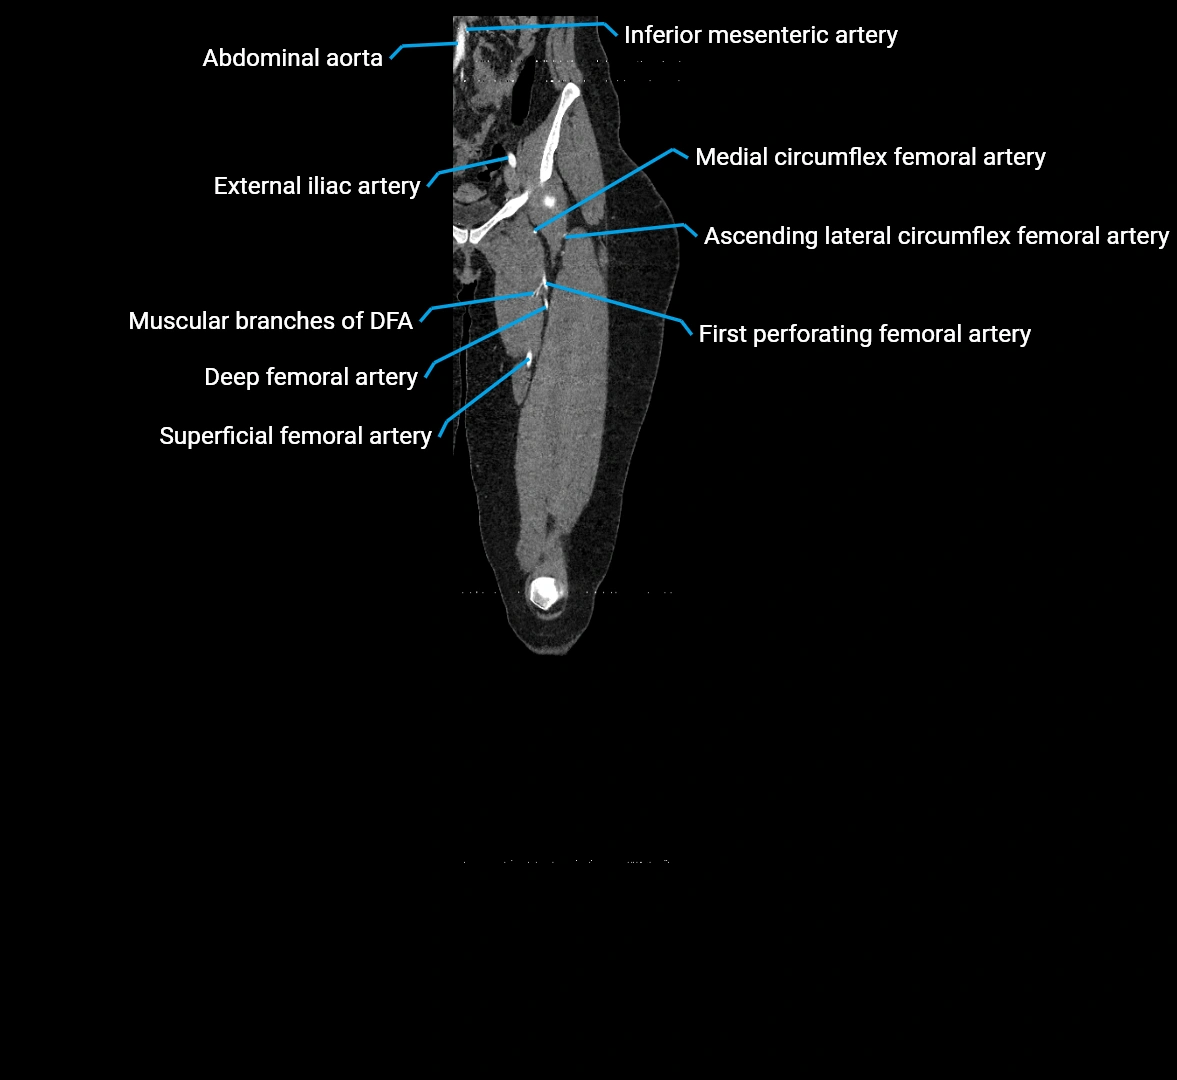

Contrast-enhanced CT (CTA):

• Gold standard for abdominal aortic imaging

• Provides excellent detail of lumen, wall, aneurysm, thrombus, and branch vessels

• Multiplanar and 3D reconstructions help in aneurysm measurement, stent graft planning, and dissection evaluation

CT images

image